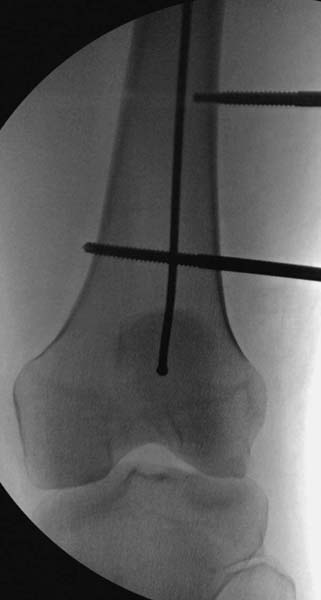

> Больная стабильная после хирургических мероприятии и получив добро,

> приступили к закрытому вправлению таранной кости с укладкой наружного

> фиксатора. Затем укладка больную на бок и открытый остеосинтез

> Остеосинтез бедра не стали делать из-за множественных переломов ребер с

> ушибом грудной клетки и поэтом у закончили фиксацию бедра наружным

> фиксатором.